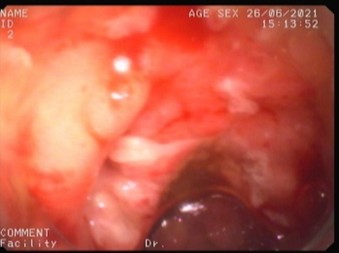

Refer to caption

Figure 1: Examples of colorectal polyp morphologies observed during colonoscopy. (a) Sessile polyp lying flat against the colonic mucosa, making detection more challenging.(b, c) Pedunculated polyps with stalk-like structures protruding from the mucosal surface.

Colorectal polyps generally exhibit two distinct morphologies: sessile (flat) and pedunculated (stalked) as shown in Fig.1. Sessile polyps, which are now recognized as more prevalent than once believed, are particularly challenging to detect during colorectal cancer screening due to their flat structure that closely adheres to the mucosal surface of the colon. In contrast, pedunculated polyps resemble a mushroom-like structure, protruding from the mucosal lining and connected by a narrow, elongated stalk [13] .